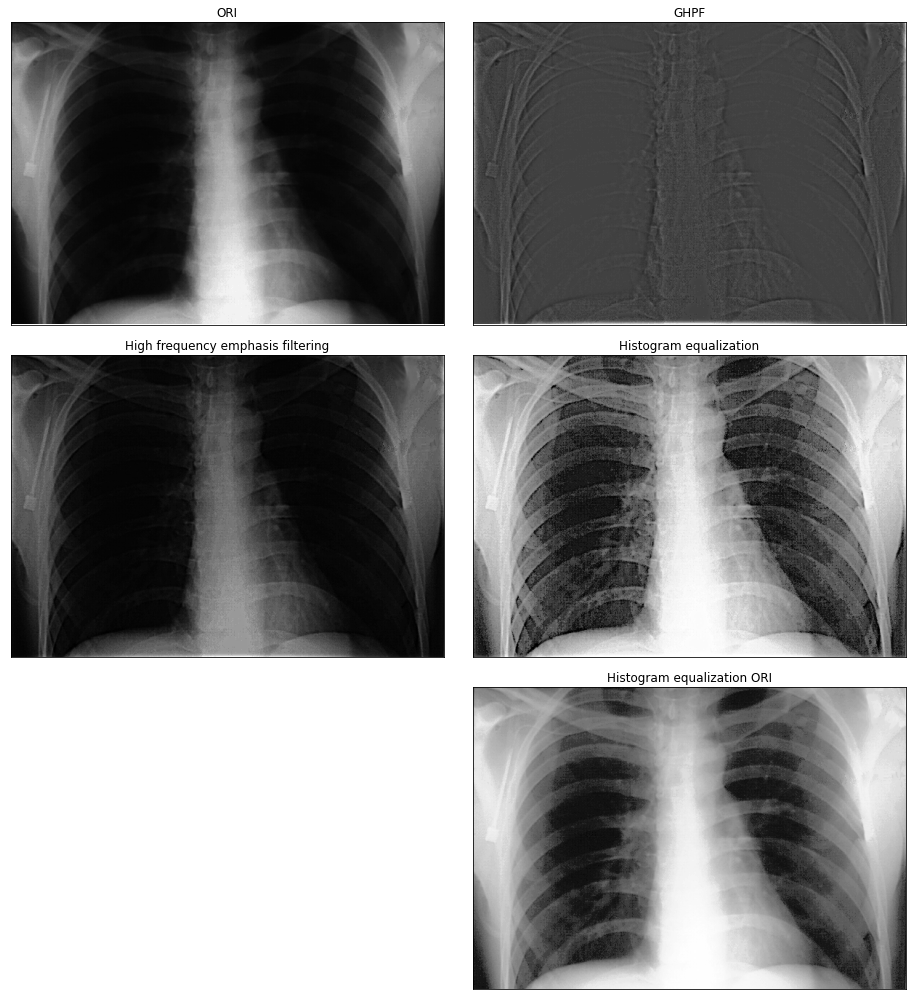

# 从图像来看,确实优于单独使用其中一种方法得到的结果,但直接对原图进行直方图均衡化,也能得到不错的结果。

img_ori = cv2.imread('DIP_Figures/DIP3E_Original_Images_CH04/Fig0459(a)(orig_chest_xray).tif', -1)

M, N = img_ori.shape[:2]# 填充

fp = pad_image(img_ori, mode='constant')

fp_cen = centralized_2d(fp)

fft = np.fft.fft2(fp_cen)# 滤波器

GHPF = gauss_high_pass_filter(fp, fp.shape, radius=70)

# 滤波后的图像

img_new = frequency_filter(fft, GHPF)

img_new = img_new[:M, :N]#=======高频增强滤波===================

k_1 = 0.5

k_2 = 0.75

res = fft * (k_1 + k_2 * GHPF)# 反变换

ifft = np.fft.ifft2(res)# 取实数部分

gp = centralized_2d(ifft.real)

g = gp[:M, :N]

g = np.clip(g, 0, g.max())temp = np.uint8(normalize(g) * 255)

img_res = cdf_interp(temp)hist_ori = cdf_interp(img_ori)plt.figure(figsize=(13, 14))

plt.subplot(3, 2, 1), plt.imshow(img_ori,'gray'),plt.title('ORI'), plt.xticks([]), plt.yticks([])

plt.subplot(3, 2, 2), plt.imshow(img_new,'gray'),plt.title('GHPF'), plt.xticks([]), plt.yticks([])

plt.subplot(3, 2, 3), plt.imshow(g,'gray'),plt.title('High frequency emphasis filtering'), plt.xticks([]), plt.yticks([])

plt.subplot(3, 2, 4), plt.imshow(img_res,'gray'),plt.title('Histogram equalization'), plt.xticks([]), plt.yticks([])

plt.subplot(3, 2, 6), plt.imshow(hist_ori,'gray'),plt.title('Histogram equalization ORI'), plt.xticks([]), plt.yticks([])

plt.tight_layout()

plt.show()